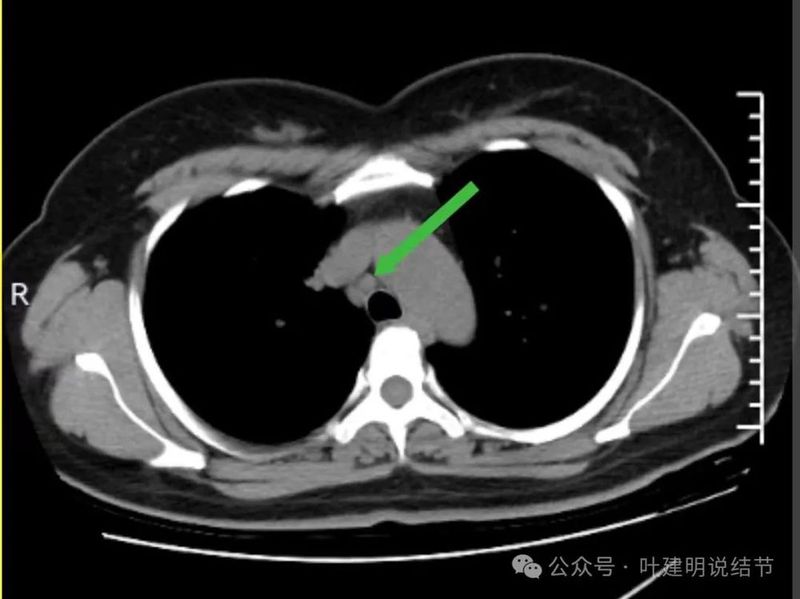

当时隆突下淋巴结小,说不上明显异常。

上腔静脉旁淋巴结也不大。